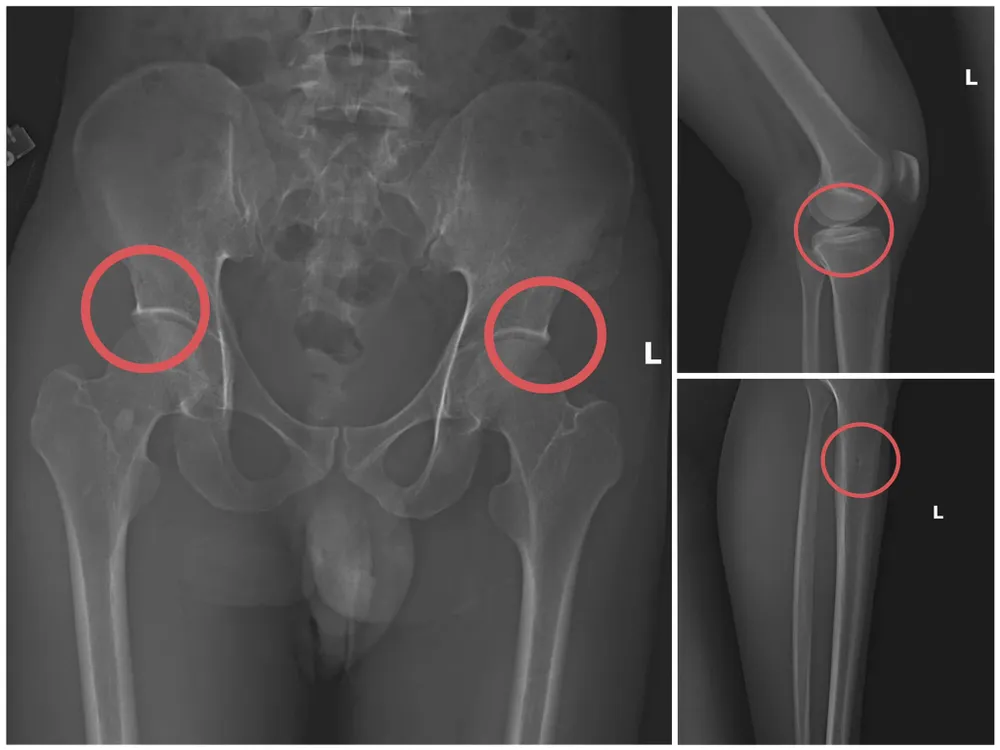

Theo cơ quan công an, đáng chú ý, đối tượng này đã trực tiếp thực hiện hành vi tiêm thuốc mê, rồi dùng kim tiêm, búa đinh để tác động vào xương người mua bảo hiểm, tạo nên các vết nứt, vỡ xương tương tự như tai nạn thật. Khi thương tích đã tạo xong, Châu tiếp tục hướng dẫn các đối tượng dựng hiện trường giả như điện giật ngã, trượt chân ngã suối nhằm hợp thức hóa bệnh án và hoàn thiện hồ sơ yêu cầu chi trả.

Bản phim chụp X-quang một số tổn thương xương do đối tượng tạo ra. Ảnh: CÔNG AN PHÚ THỌ

Theo đánh giá của Thiếu tướng Nguyễn Minh Tuấn, Giám đốc Công an tỉnh Phú Thọ, thủ đoạn của các đối tượng vừa tàn nhẫn, vô nhân tính, coi thường sức khỏe, tính mạng của con người; các đối tượng tính toán kỹ để gây thương tích đúng vị trí có mức chi trả cao, khiến các công ty bảo hiểm khó phát hiện dấu hiệu gian dối.